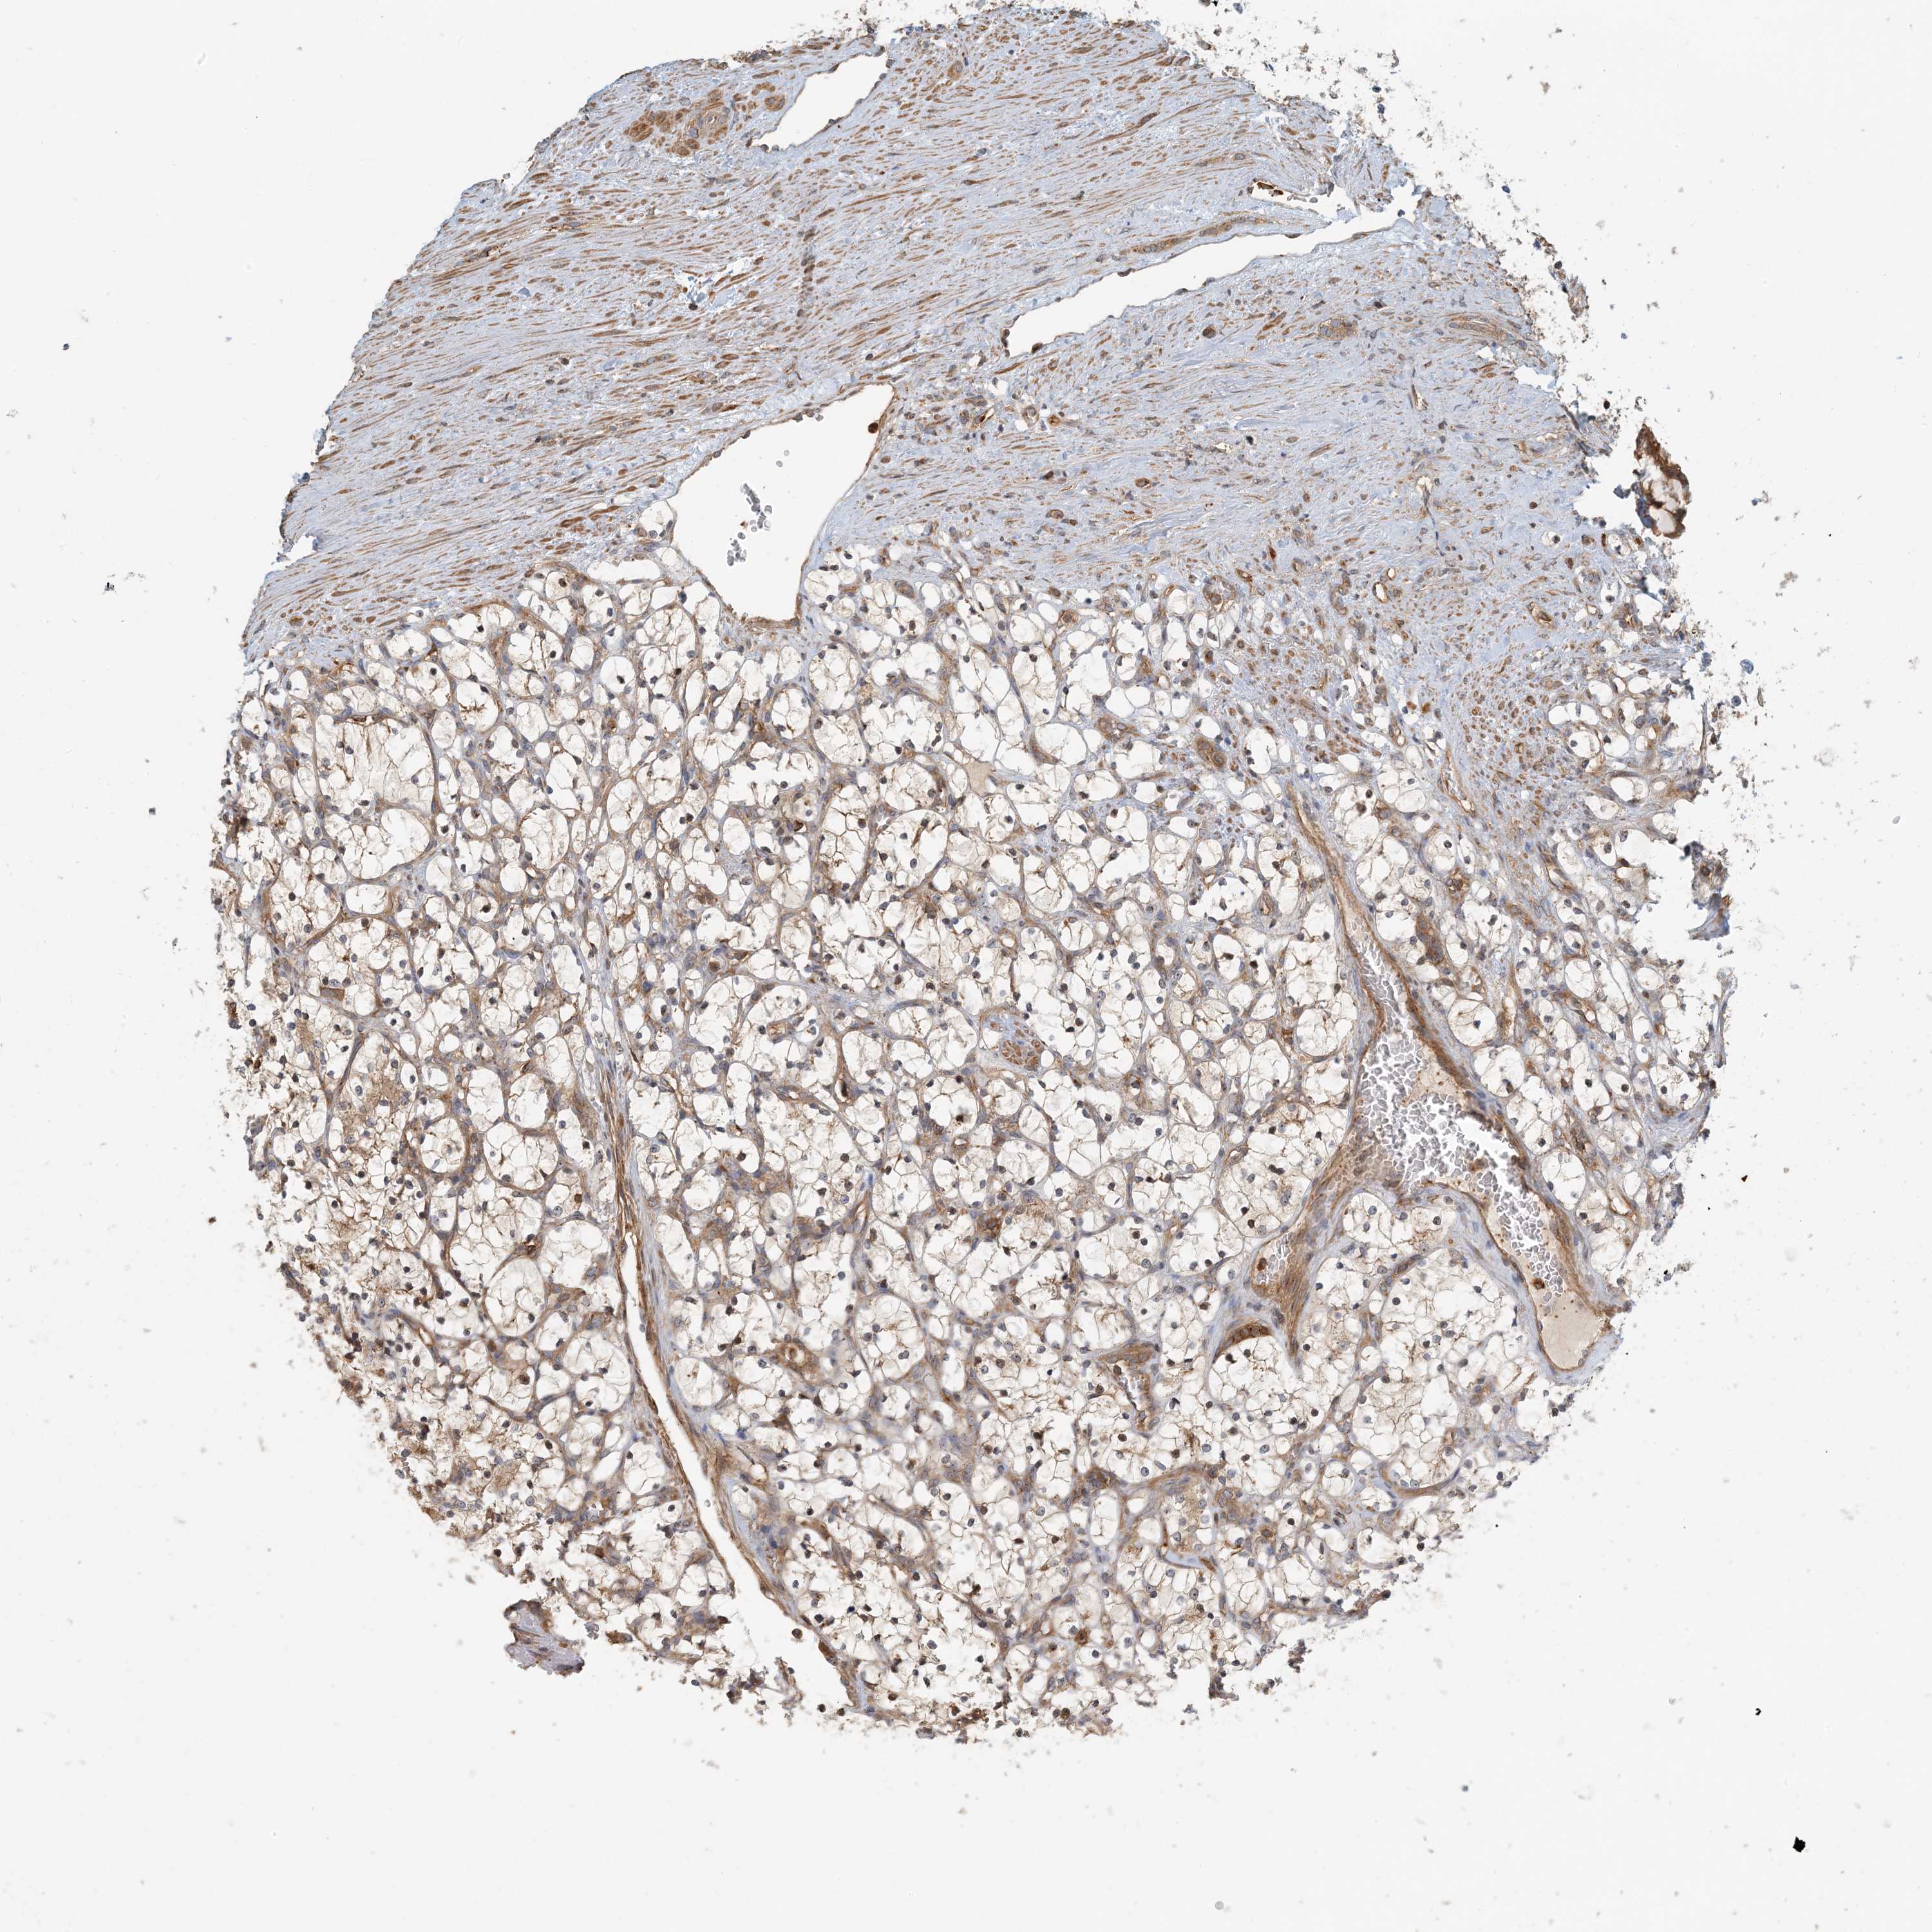

Average pTPM 1.3

Number of samples 64